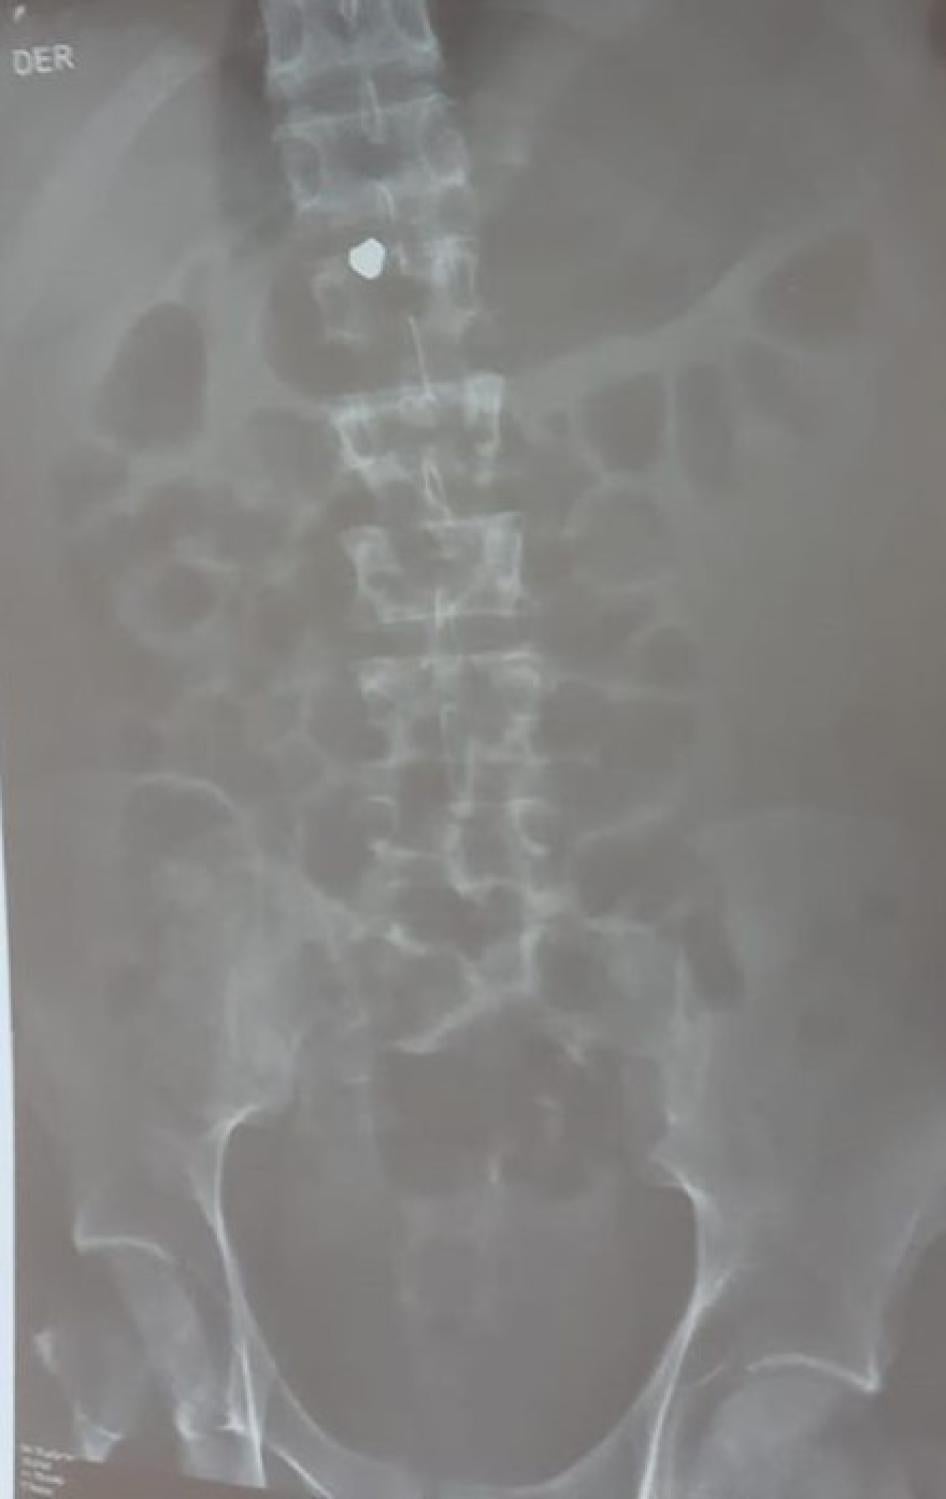

- Also at around 9:50 p.m., Jon Cordero, 24, a protester, was struck by a pellet that lodged in his spinal cord, paralyzing his lower body, his aunt said. Surgeons told the family that based on the X-rays they believed the pellet was lead, and said Cordero is unlikely ever to walk again.